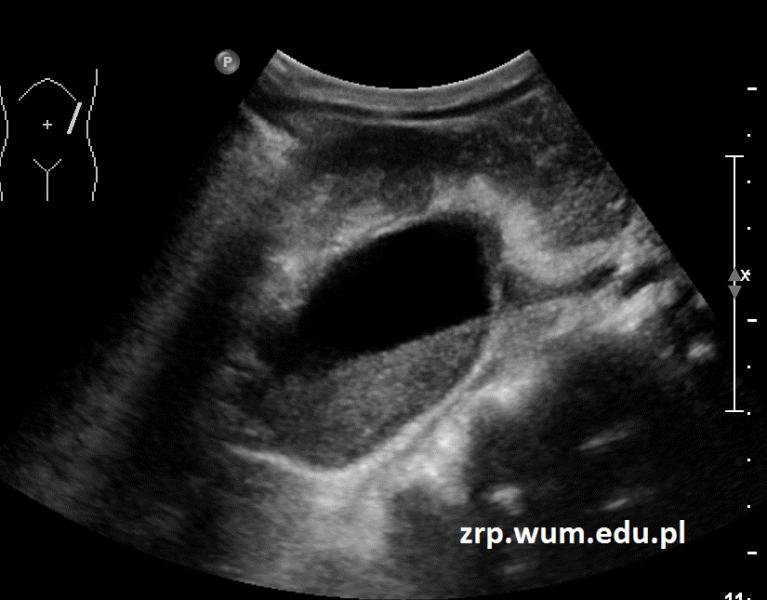

Przypadek 39: 6-letnia dziewczynka przyjęta do Szpitala z powodu powikłanego ostrego odmiedniczkowego zapalenia nerek. W badaniach moczu - ropomocz.

Rozpoznanie: W badaniu USG uwidoczniono roponercze nerki lewej - poszerzony UKM, wypełniony echogenną gęstą treścią (na zdjęciu widoczny poziom gęstej treści w poszerzonej miedniczce).